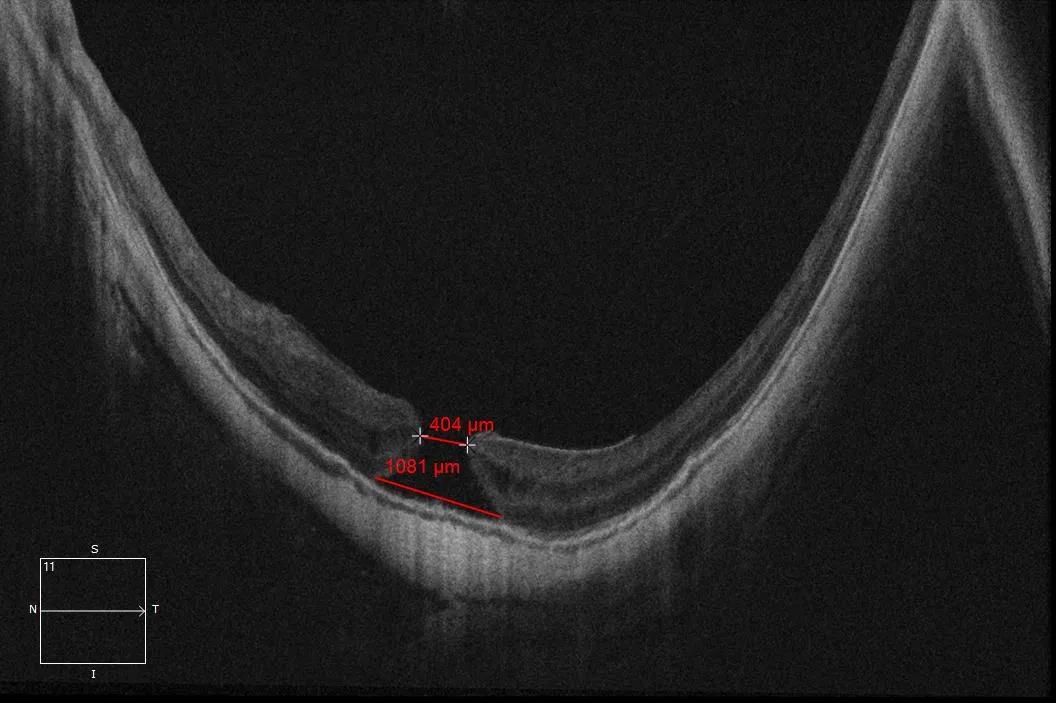

做完检查拿着报告单的鲍先生已是忧心忡忡,沮丧着头将检查结果递给了许院长,许院长看完鲍先生的眼底OCT检查结果报告轻声的告诉他:“老人家,您这个是眼底黄斑裂孔,不是什么白内障啊,需要马上做手术。”还未缓过神的鲍先生惊愕的问道:“这是什么病啊?这么严重,需要做手术吗?”许泽骏院长耐心的解释到:“这个眼底OCT检查结果图上可以清楚看到有一个404μm缺口,这个就是黄斑裂孔。您的视力很差,且看东西变形,都是他它惹的祸,这是一种常见特发性黄斑裂孔,会严重损害您的中心视力,是因为眼睛内黄斑部视网膜内界膜至感光细胞层发生的组织缺损,因而常被大众称为眼睛里面破了一个洞。”

鲍先生眼底黄斑裂孔 404um

“特发性黄斑裂孔形成过程主要分为四期,发病初期视力会有轻度下降,数日或数月后视力还会出现进一步下降,而您的眼底OCT检查结果显示黄斑裂孔有404μm,属于III期阶段,目前建议您尽快手术,一方面是避免视力再次下降而导致的视力缺失等不可逆后果,另一方面希望能通过手术帮助恢复视力的可能。”许院长说道。